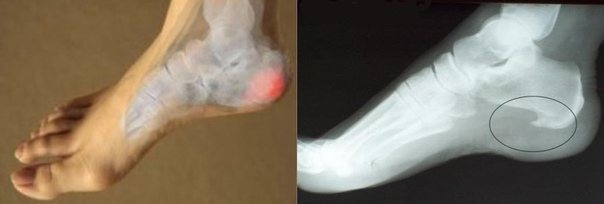

Врачи диагностируют пяточную шпору при возникновении рядом с бугром пяточной кости выроста, который становится причиной развития воспалительного процесса и сильной боли у пациента. Если вовремя не начать лечение, размеры пяточной шпоры могут увеличиться до 12 сантиметров.

Такое заболевание встречается достаточно часто у жителей крупных городов. При этом большую часть пациентов составляют женщины. Основным симптомом выступают сильные и резкие боли в области пятки, когда человек наступает на ногу.